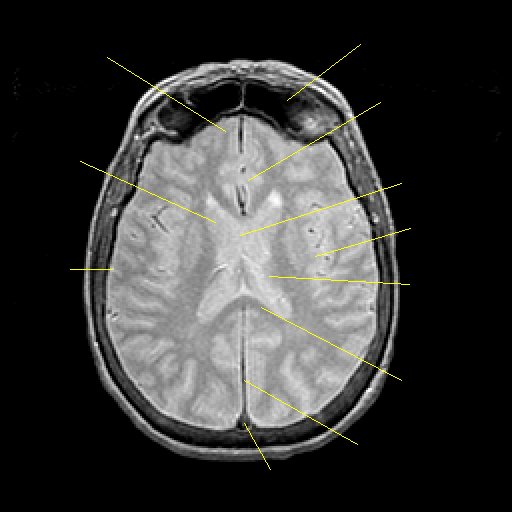

Proton density-weighted structural MR: Slice 31

Slice 31

Pointers

Labeled